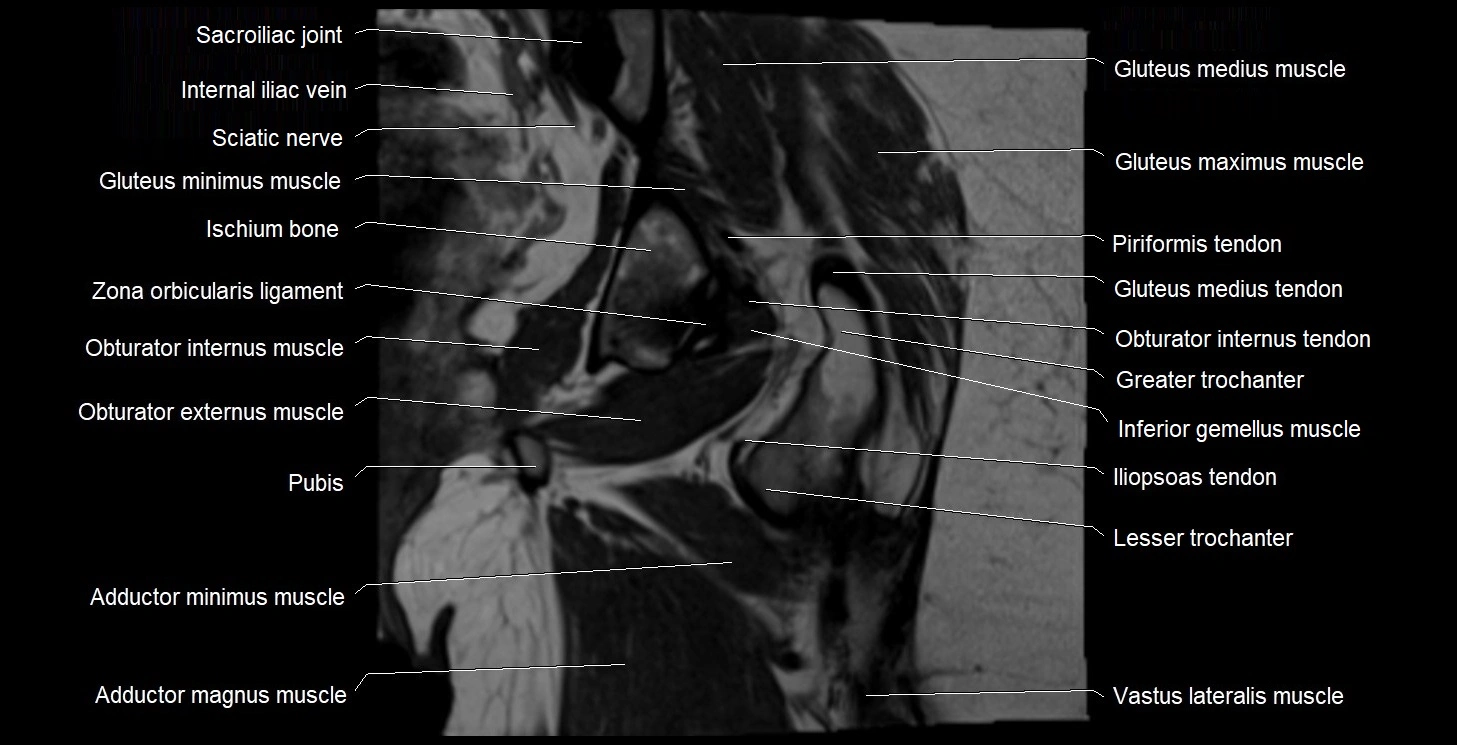

- Gluteus medius muscle

- Gluteus medius tendon

- Gluteus minimus muscle

- Greater trochanter

- Inferior gemellus muscle

- Ischiofemoral ligament

- Lesser trochanter

- Obturator internus muscle

- Obturator internus tendon

- Sacroiliac joint

- Sacrospinous ligament

- Vastus lateralis muscle

- Zona orbicularis ligament